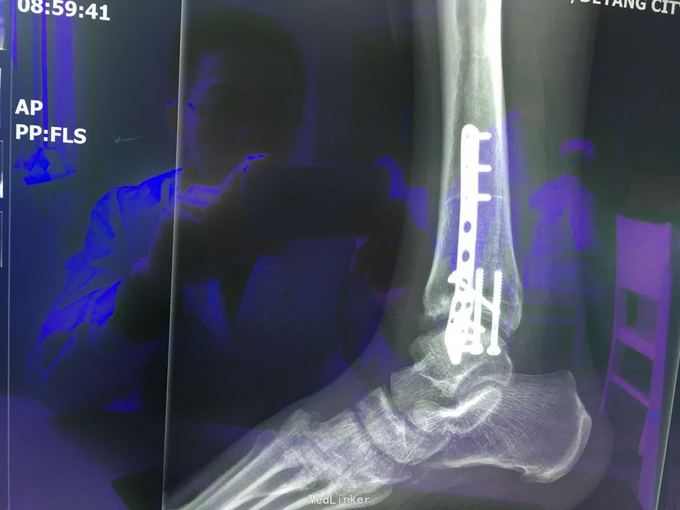

查体:左肾区叩痛,无皮肤隆起,未扪及肿块;腰椎压痛,活动受限,双下肢感觉存在,右小腿石膏托外固定,有踝关节明显肿胀,局部压痛活动受限,指端感觉血运可。 CT及X片:L2、L4椎体爆裂性骨折,L1-L4左侧横突骨折,右坐骨支骨折,右侧胫骨内、后及右侧腓骨外踝骨折,右足第1-4跖骨向外侧脱位及半脱位,伴近端斯脱性骨折。左肾挫裂伤,左肾重度积水,左肾周血肿。

诊断:右足lisfrance损伤,左肾挫裂伤;左肾周血肿,左侧输尿管结石伴左肾重度积水,L2、L4椎体骨折,L1-L4左侧横突骨折,右侧坐骨支骨折,右三踝骨折,全身多处皮肤软组织挫伤 处理:急诊行左肾探查,左肾切除术,择期行经后路腰2、4椎体骨折切开复位、椎公根螺钉内固定术+右内、外踝骨折切开复位内固定术,择期行右足lisfrance关节复位克氏针内固定术。